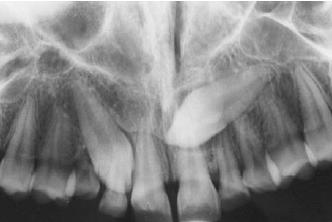

答:若真的等待了数个月后还是不见恒牙,那么家长们就要带孩子到诊所去让牙医做个详细的检查。一般来说,牙医都会利用X光片做检查。

·多生牙就是两颗门牙的中间有多生牙挡着,使到正常的恒牙无法萌出。这样的情形多数需要先把这颗多生牙拔除,新牙才能长出。